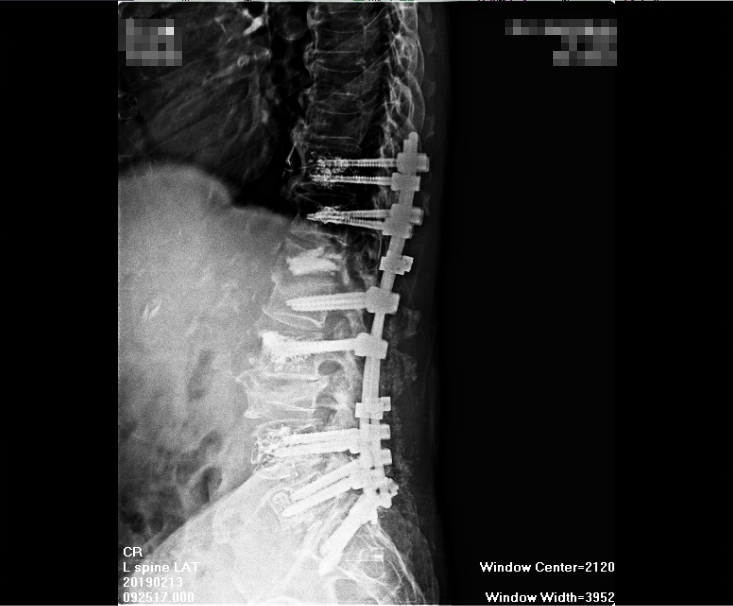

老先生家屬說他原本身體健壯,活動自如,但前兩年腰臀痛後檢查是腰椎滑脫,結果這兩年開了四次刀(包第一次括離譜的開錯部位的刀),結果,經歷四次開刀後,老先生又仍是腰腿痛麻,原本的疼痛沒有消失不說,幾次開刀後,腰上長達幾十公分刀疤,及腰椎上釘了18支鋼釘,讓老人家每天都痛不欲生,老先生家屬束手無策,卻又不知如何解決問題。

第三慘,第四次開刀完成,打了18支鋼釘,背後刀疤數十公分,鎮日疼痛,

四次大手術造成的損傷,別說這是個年近八旬的老者,就算是個壯漢,在同一個地方給他開幾次刀,上面打了這麼多鋼釘和固定板,當受傷的肌纖維形成緊縮狀態,在骨組織與鋼釘間滑動,結疤的地方這麼大,肌纖維收縮的如此嚴重,身上又有許多不屬於自己的鋼釘鋼板,光想像就令人毛骨悚然,光想像就讓人痛苦不堪,還被家人懷疑精神有問題,老先生真的只能無語問蒼天了!

就算硬組織異變在術後獲得改善,但術後軟組織形成的沾黏,肌體攣縮使活動及血循問題更加重,這也是必然,問題未解決,反而加重病況,開刀的選擇怎麼看也不對!況且,開刀所造成的傷害,是永遠無法視若無睹,常是<起手無回>,很難翻身!